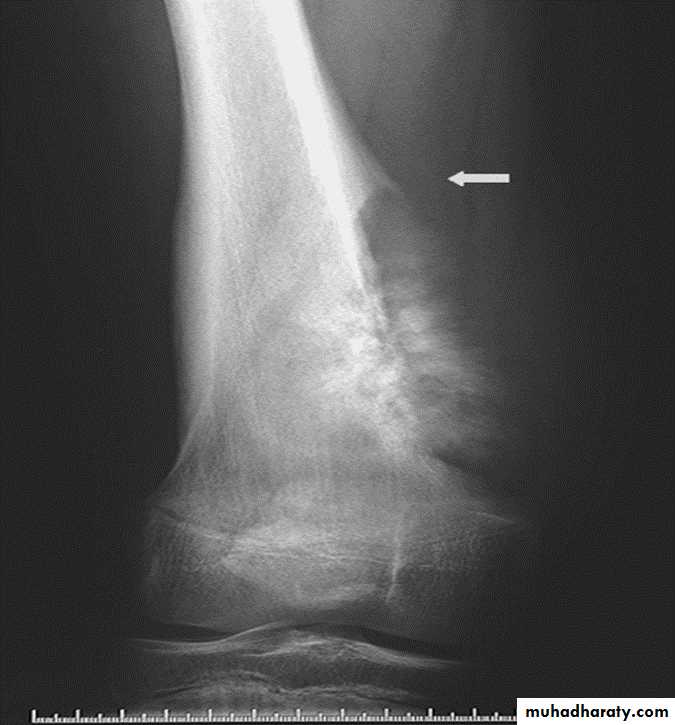

Benign or malignant ????Codman's triangle: Elevation of the periosteum at the side of the tumor margin

*Codmans triangle seen in malignant bone tumor (OS)

Codman's triangle is a type of periosteal reaction seen with aggressive bone lesions could be singlelayer and mulitlayered periosteal reaction), only the edge of the raised periosteum will ossify.